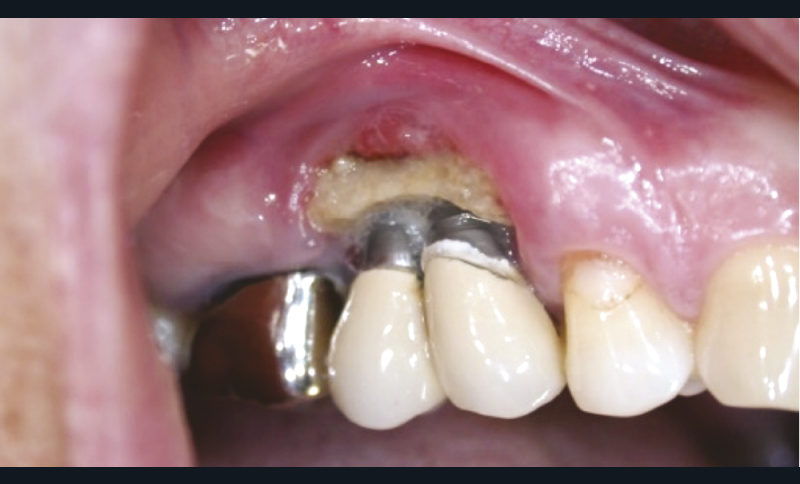

2. Ostéonécrose après pose d’implant dans un contexte oncologique (BP IV cancer du sein).

• Certains inhibiteurs de la résorption osseuse que sont les bisphosphonates (BPs), ainsi que les anticorps monoclonaux anti-RANK-L (denosumab) sont à l’origine d’ostéonécrose des mâchoires (ONM) (fig. 2). Ces traitements sont indiqués à la fois dans des pathologies bénignes (ostéoporose, maladie de Paget, etc.) ou malignes (métastases osseuses de tumeurs solides, myélome) avec des risques d’ONM variables. Le risque est important dans les indications oncologiques, de l’ordre de 1 à 20 %, et nettement plus faible dans les indications bénignes, de 0,001 % à 0,1 % [23]. Il est actuellement contre-indiqué de réaliser la chirurgie implantaire chez des patients traités par des inhibiteurs de la résorption osseuse (BPs ou denosumab) dans des indications malignes. Pour autant, la chirurgie implantaire n’est pas contre-indiquée chez les patients traités par des BP per os ou du denosumab dans des indications bénignes, en l’absence de comorbidités et dans un temps de traitement de moins de cinq ans [23].